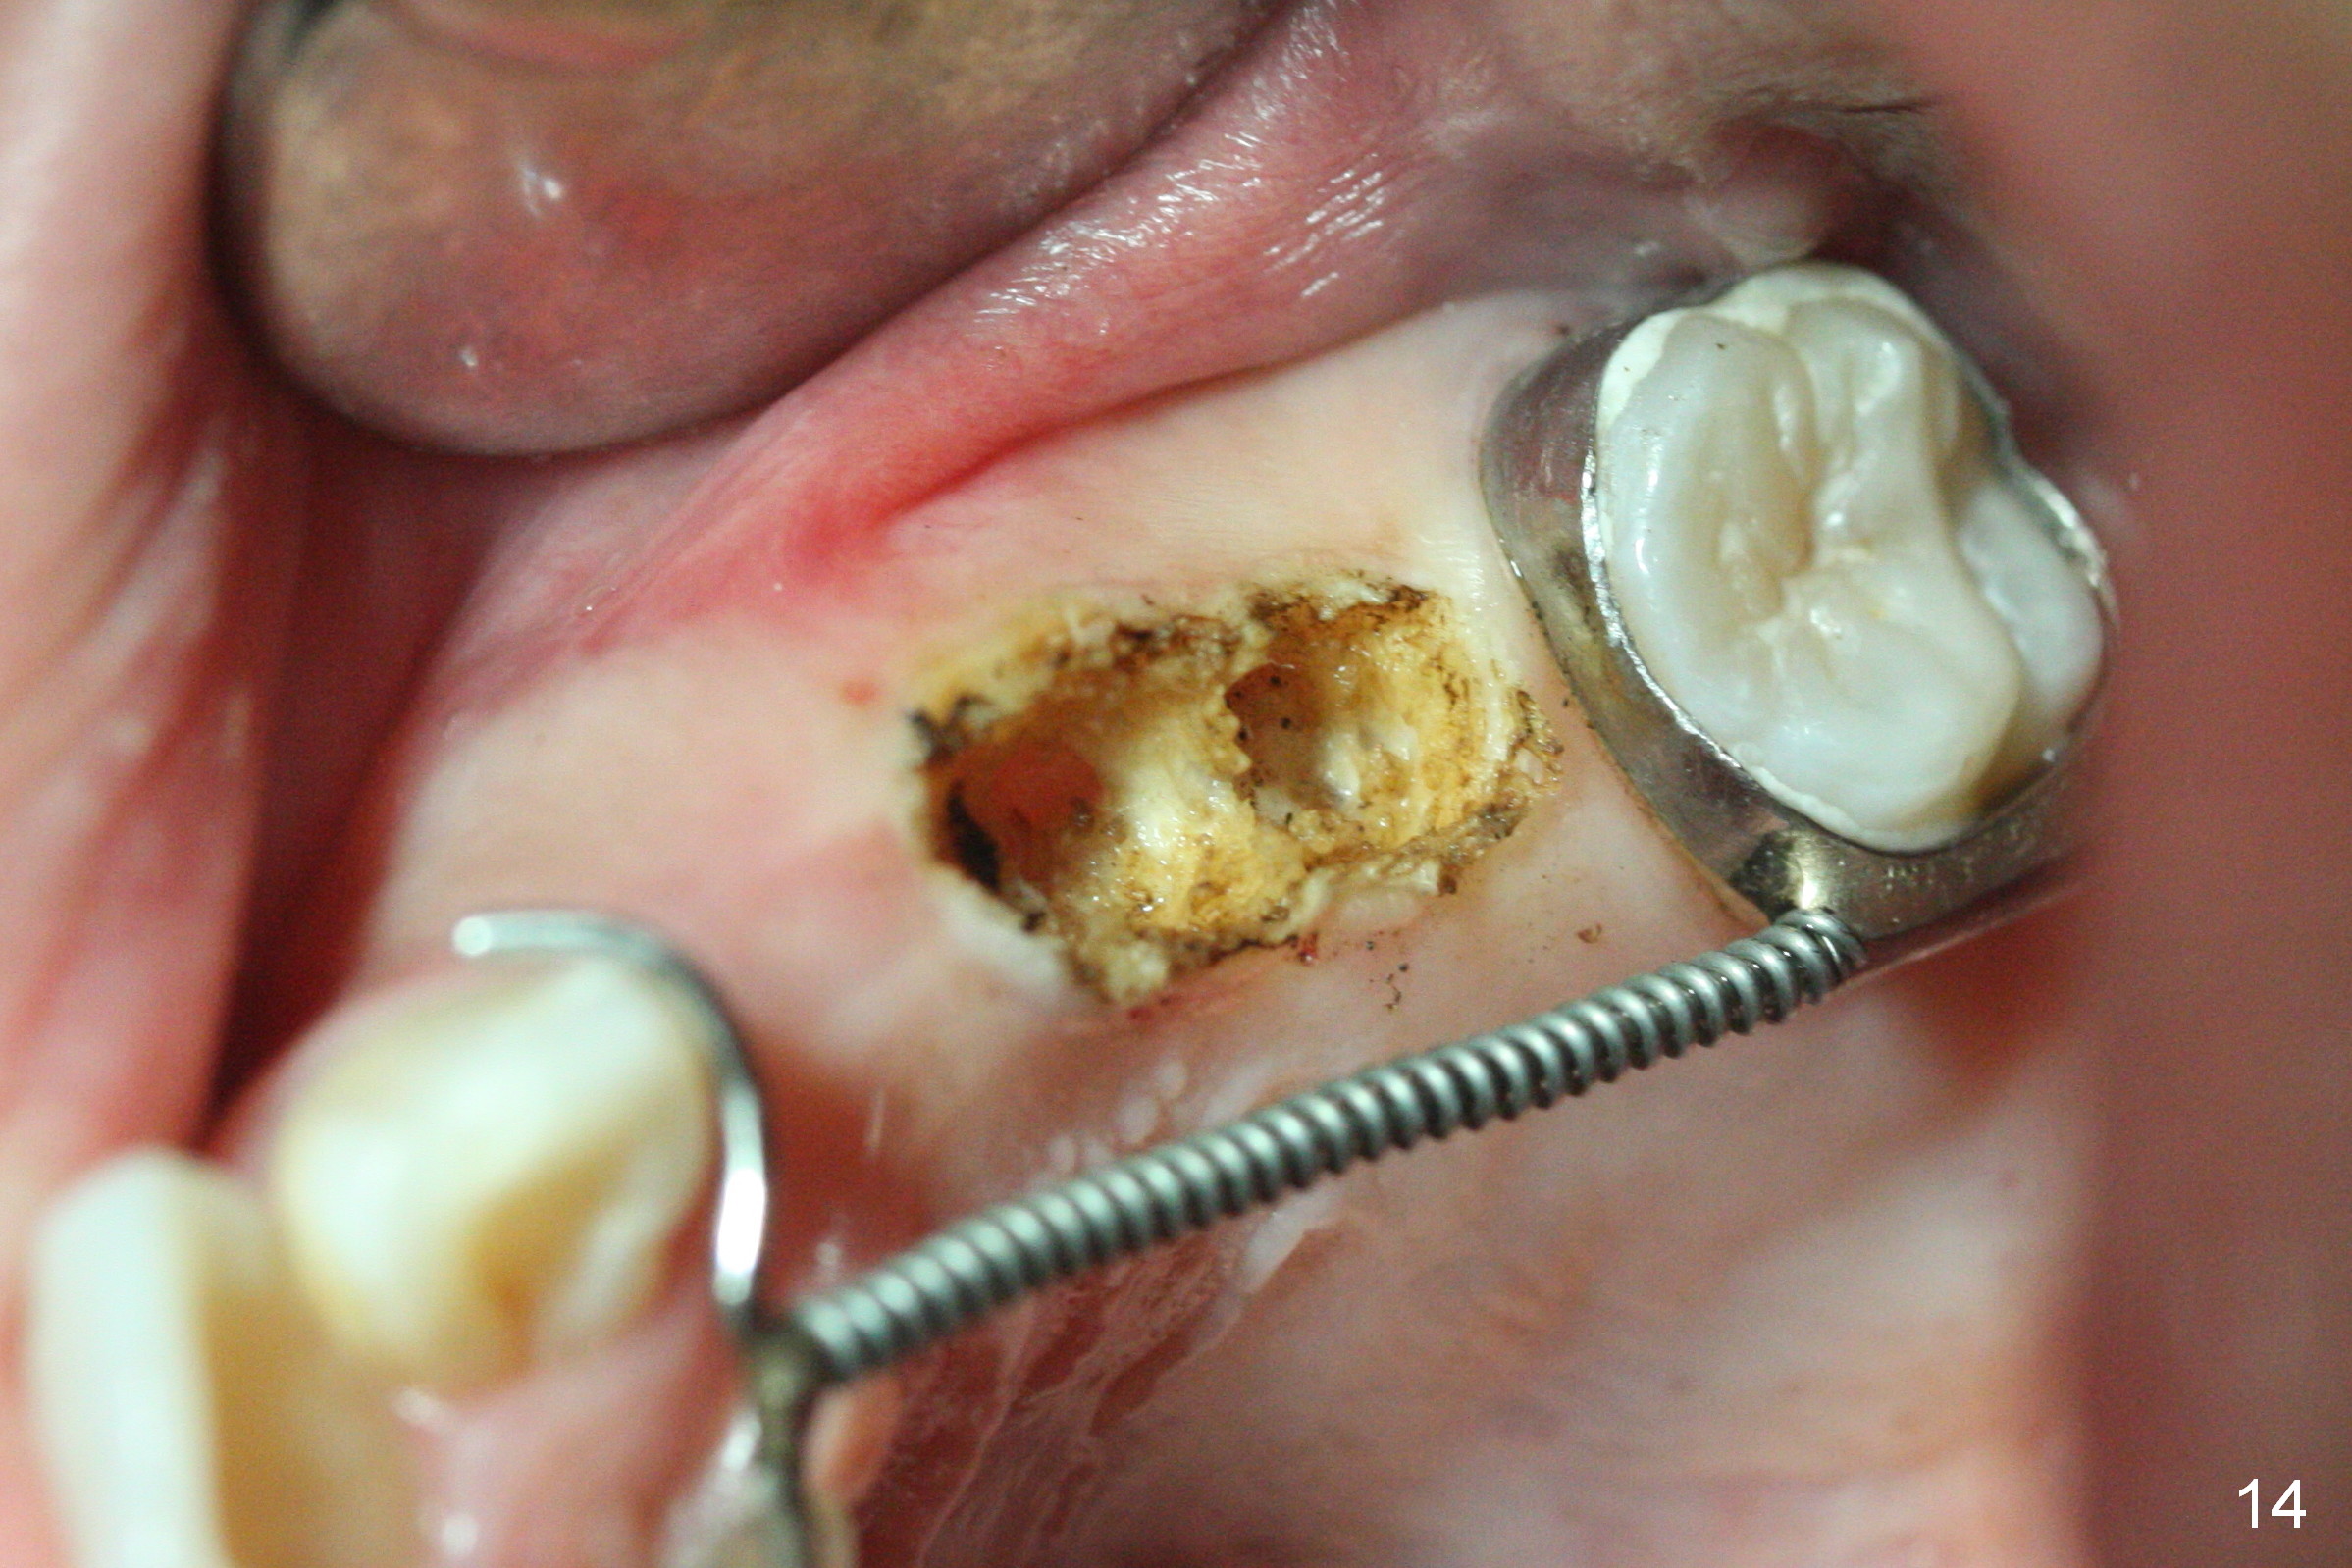

Nearly 2 months post regainer placement, UL6 appears to have been distalized (Fig.11 arrow), but UL4,5 have not erupted (Fig.12), while UL1,2 are displaced (Fig.13). Diode laser is used to expose the tooth buds, which are deeply seated (Fig.14). If they do not erupt soon, a mini implant should be placed for anchorage (Fig.10). Use several power chains to retract the anterior arm, while drill through the Nance appliance (high speed handpiece) for mini implant placement.